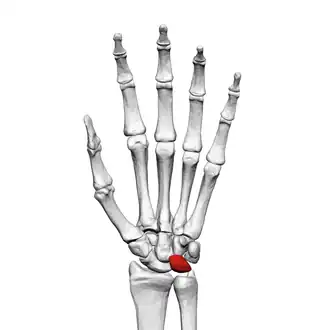

![]() Left hand anterior view (palmar view). Lunate bone shown in red. | |

The lunate bone (semilunar bone) is a carpal bone in the human hand. It is distinguished by its deep concavity and crescentic outline. It is situated in the center of the proximal row carpal bones, which lie between the ulna and radius and the hand. The lunate carpal bone is situated between the lateral scaphoid bone and medial triquetral bone.

Lunate bone of the left hand (shown in red). Animation. -